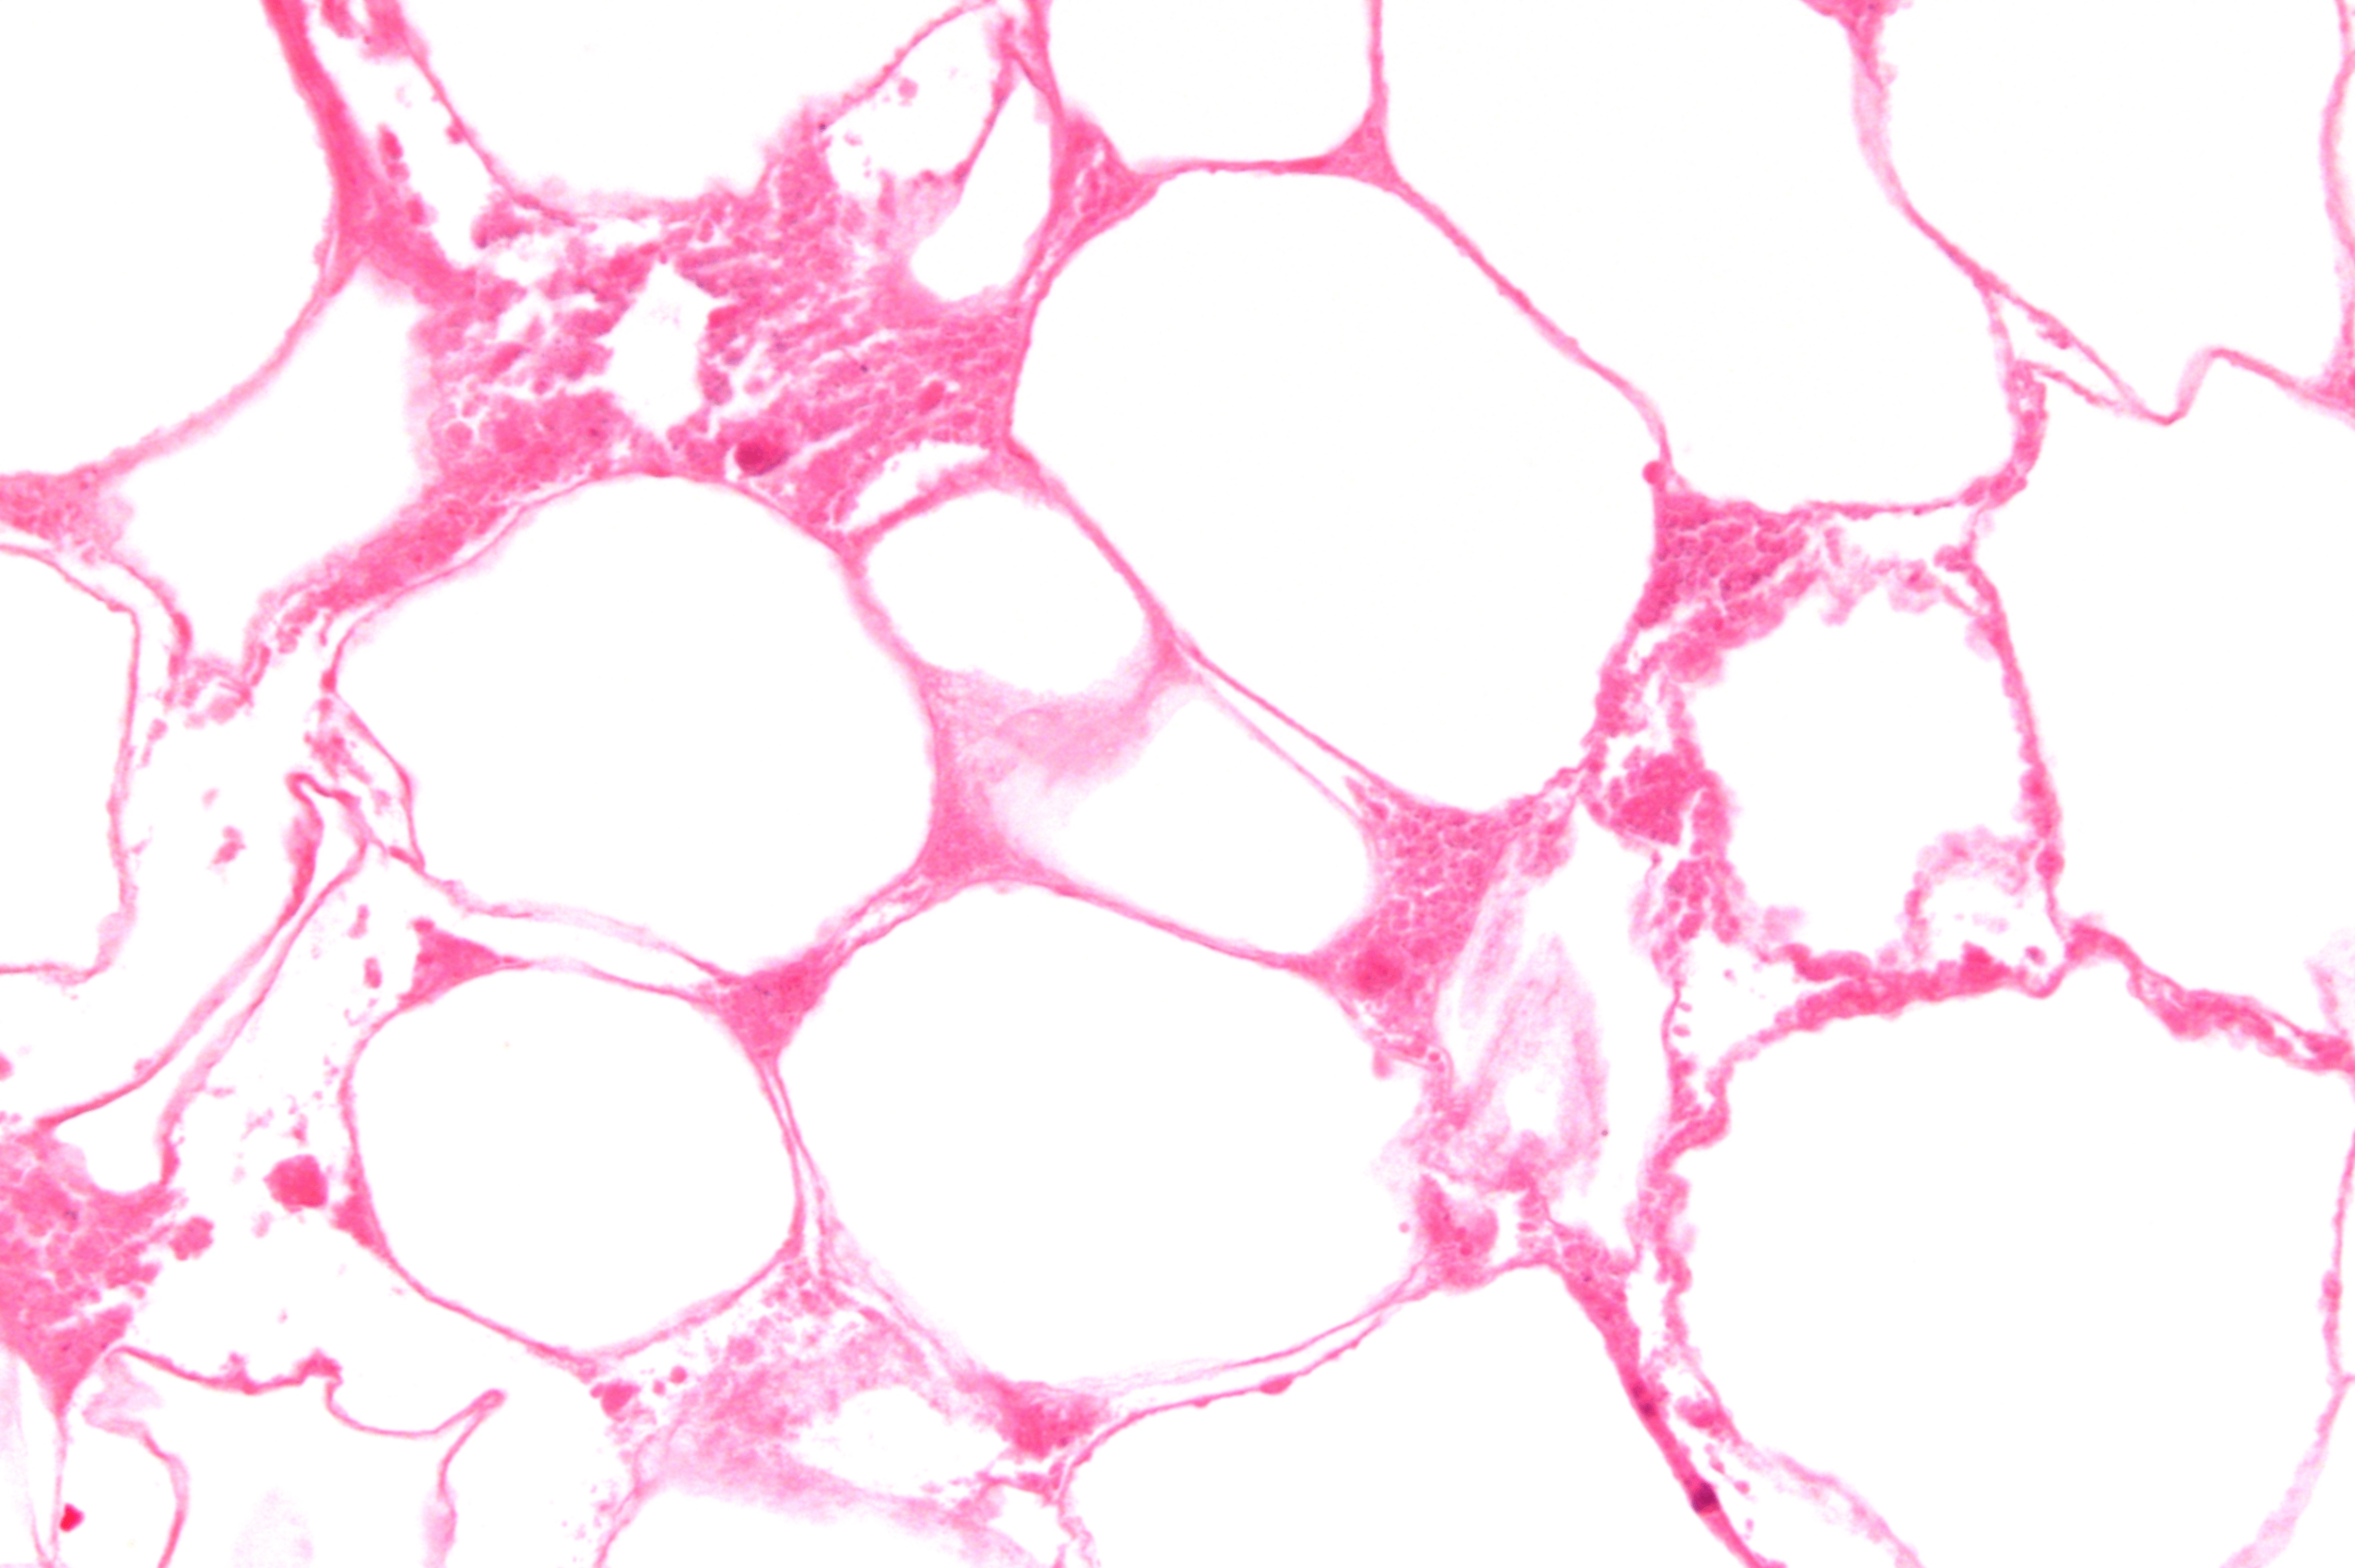

지방괴사(Fat) | • 지방 분해효소(리파아제)에 의해 중성지방 → 지방산 • 지방산 + 칼슘 → 비누화(saponification) | •분홍색 무정형 침착물 • 비누 같은 외관 • 종종 석회화 동반 | • 급성 췌장염 시 복막 지방 조직 • 유방 외상성 지방괴사 |

Fat necrosis, Wikimedia Commons